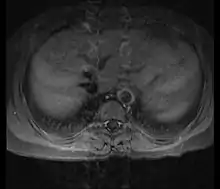

| Left anterior oblique angiographic image of Takayasu's arteritis showing areas of stenosis in multiple great vessels | |